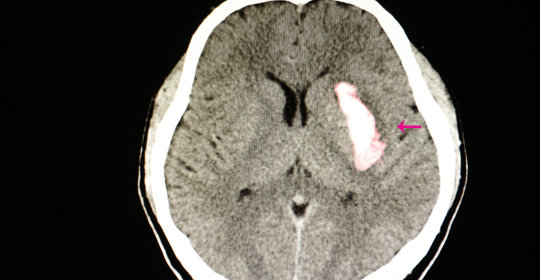

硬腦膜外血腫:破解腦部危機,看懂這些症狀,掌握治療方法

硬腦膜外血腫是常見的顱腦傷害之一,可導致顱內壓升高和神經功能障礙。瞭解硬腦膜外血腫的症狀和治療方法有助於及時診斷和治療,降低併發症和死亡率。本文詳細介紹了硬腦膜外血腫的症狀、診斷、治療和預防方法,旨在提高公眾對這一腦部危急病症的認識。